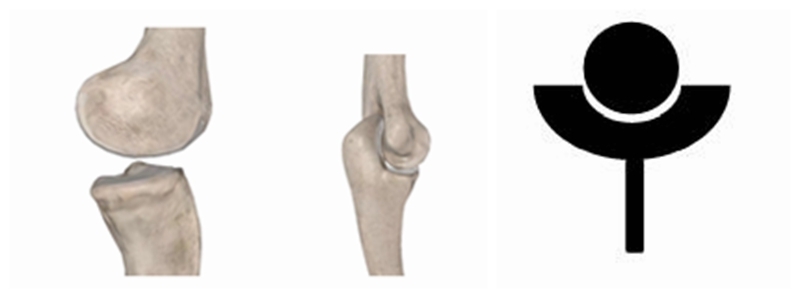

首先是RTSA的设计。仔细观察人体的各个关节的特点,我们可以发现一些规律。人体关节大致可以分为两大类。一类是像肩、髋这样的近躯干关节,近端为“杯”,而远端为“球”。

另一类则像膝、肘这样的远端关节,近端为“球”,远端为“杯”。

医学先驱们早期在设计人工肩关节假体时所采取的方案便是尽可能还原自然肩的解剖结构,故所有的方案均设计为近心端为“杯”,远心端为“球”。部分研究者甚至为了增加关节的稳定性,而刻意将“杯”设计的更大更深,类似于人类的髋关节,但后来证明增加稳定性反而让失败率增加,故这种设计很快便被放弃。而RTSA则是翻转了自然肩的解剖特点,将“球”“杯”倒置,让原本类似于“髋”的关节变得更像“肘”或“膝”一样。这一颠覆性的改变最终让人工肩关节置换的许多困难和疑惑迎刃而解,许多情况下其远近期疗效均有明显提高。